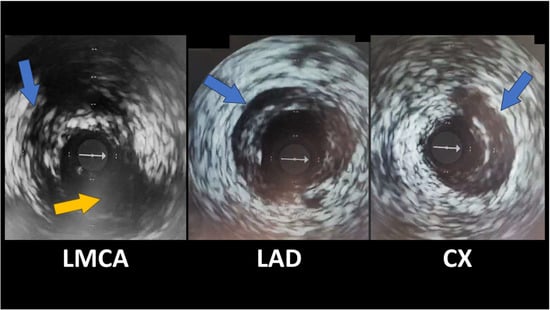

OCT and IVUS enable direct, real-time visualization of the coronary artery wall’s structure, providing additional information compared with simple angiography (Figure 3). Both modalities can identify the characteristic features of SCAD: the presence of a double lumen (true and false) separated by an intimal flap, the delineation of an intramural hematoma, and the absence of atheromatous plaques that would suggest typical coronary artery disease [,].

IVUS revealing spontaneous coronary artery dissections (blue arrows); Cx emergence from LMCA (yellow arrow). The white arrow indicates the IVUS guidewire.

Thus, IVUS/OCT can confirm the diagnosis in angiographically dubious lesions (e.g., Type 3 SCAD mimicking atherosclerotic stenosis) and can prevent both false negatives (missed dissections) and false positives (atherosclerotic lesions misinterpreted as dissections) [].